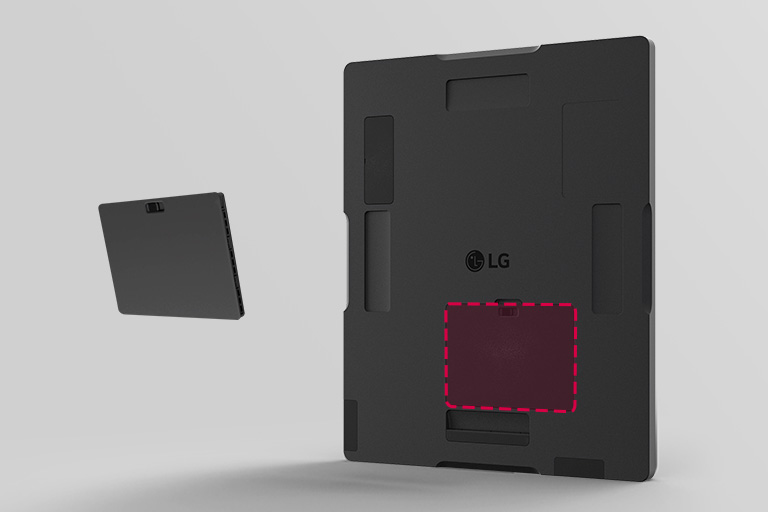

Ununterbrochene Nutzung für längere Betriebszeiten

*300 Aufnahmen / 7,5 Stunden bei einer Zykluszeit von 90 Sek.

Verbesserter Komfort